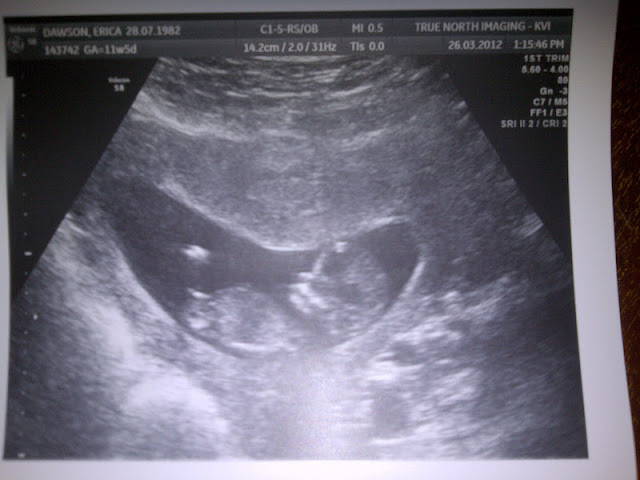

As I sit here in the quiet of the night, as you're fast asleep cuddled up to your blanket, still clutching your water bottle that you can't go to sleep without, I can't help but think about how your little life will be changed in only a few short weeks.

I know that you will be thrilled to have a tiny baby to hold, cuddle, hug, kiss and pretend that he's all yours. I know that you will take on the role of big sister as proudly and confidently as anyone ever has. Your little heart will expand just as mine will when you meet him for the first time, and a new chapter of our lives will begin the moment that he is born. A new chapter, a great chapter. There will be days when it feels like nothing has changed...where our days filled with baking, trips to the park and splash pad, dancing in the living room and playing duets on the piano will still exist. I'll make sure of that.

Just the other day I had a million thoughts running through my head as I lay in bed having contraction after contraction for several hours. Knowing that your little brother had only been growing inside of me for 33 weeks, your dad and I quickly started packing our hospital bags, talking about how we didn't want this to be happening so soon.

But you were on my mind just as much as your brother was. I started thinking about what you'd need while we were in the hospital, how much I'd miss you, what you'd be thinking having mom and dad gone for so long and how you'd react to coming into our hospital room for the first time and seeing a tiny baby wrapped up in my arms. Thankfully though, somehow the contractions settled down and dwindled to nothing, which gave us the greatest relief that you can even imagine and made me grateful for the few extra days or weeks that we were given with you as our smallest babe.